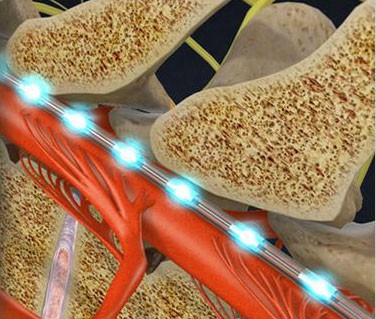

- Spinal Cord Stimulator Implant